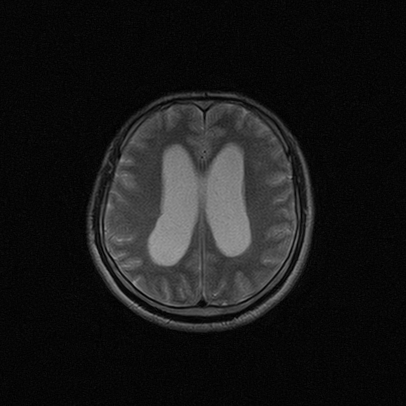

四脑室区见混杂信号占位影,脑室系统扩张明显,临近结构显著受压称位,患者52岁,多考虑室管膜瘤可能性大

考虑第四脑室室管膜瘤并阻塞性脑积水。

考虑第四脑室室管膜瘤并梗阻性脑积水;部分性空蝶鞍;左侧上颌窦粘膜下囊肿。